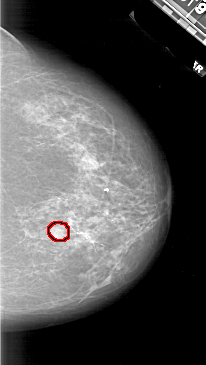

A_1827_1.RIGHT_MLO

FILE: A_1827_1.RIGHT_MLO.OVERLAY

TOTAL_ABNORMALITIES 1

ABNORMALITY 1

LESION_TYPE MASS SHAPE ROUND MARGINS ILL_DEFINED

ASSESSMENT 4

SUBTLETY 3

PATHOLOGY MALIGNANT

TOTAL_OUTLINES 1

BOUNDARY